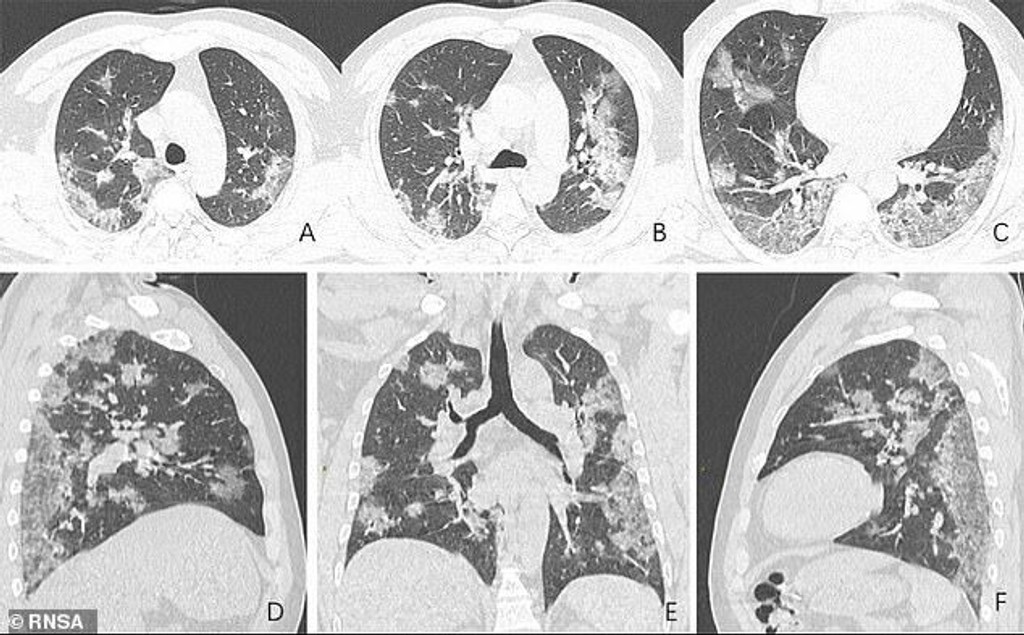

Severoamerická rádiologická spoločnosť (RSNA) uverejnila röntgenové snímky 44-ročného muža, ktorý zomrel v dôsledku nového koronavírusu. Informuje Daily Mail.

Na záberoch vidno, ako COVID-19 doslova ničí pľúca Čínana. Na spodných krajoch pľúc sa vyskytujú biele škvrny, čo odborníci nazývajú príznak „mliečneho skla".

Ide o čiastočné zaplnenie vzduchových priestorov zápalovými telesnými tekutinami. Podobné abnormality našli lekári aj pri predošlých koronavírusoch typov SARS a MERS.

Mŕtvy muž pracoval na trhu s morskými plodmi vo Wu-chane, epicentre a zdroji nákazy. Na základe snímkov A až F vidno, ako sa tekutina v jeho pľúcach postupne zväčšovala.